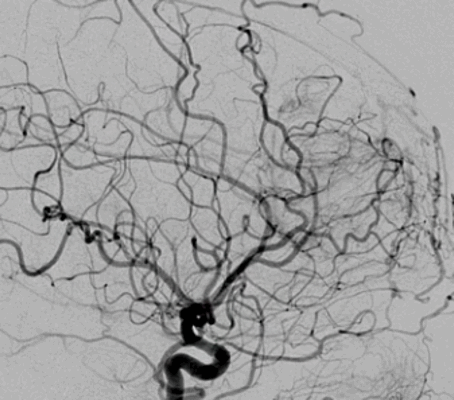

Рисунок 1. Наблюдение 1 (больной М.). а - спиральная КТ-ангиография; б - спиральная КТ с 3D костной реконструкцией; в - селективная церебральная ангиография; г - интраоперационные фотографии (этапы операции); д, е - внешний вид больного до и после операции. При проведении спиральной компьютерной томографии (СКТ) с ангиографией с 3D-реконструкцией костей свода и основания черепа определяются гипертрофированные с наличием крупных лакун вены затылочной области справа, которые через дефект в лямбдовидном шве размером 12×9,4 мм дренируются в правую половину поперечного синуса через атипичную эмиссарную вену (см. рис. 1, б). При селективной церебральной ангиографии в артериальную фазу (см. рис. 1, в) данных о наличии артериовенозной мальформации головного мозга не выявлено. Определяется атипичная вена, отходящая от правой половины поперечного синуса, дренирующаяся в экстракраниальную венозную лакуну в правой затылочной области. Больному было проведено оперативное вмешательство, которое заключалось в разобщении правой половины поперечного синуса и экстракраниальных варикозно-расширенных вен и венозных лакун. Интраоперационно отмечалось их спадание (см. рис. 1, г). Трофических изменений кожного лоскута не выявлялось. Больной был выписан под наблюдение невролога (см. рис. 1, е).

В случае пациента Д. проведения МРТ и спиральной компьютерной ангиографии головного мозга явилось достаточным для установления диагноза. В случае пациента М. данные спиральной КТ неубедительно указывали на отсутствие артериовенозного шунтирования.

Целью селективной церебральной ангиографии при SP является исключение другой сосудистой патологии, характеризующейся артериовенозным шунтированием, а при обнаружении SP - подробное изучение его ангиоархитектоники, идентификация всех венозных коллекторов, соединяющих синус и экстракраниальное образование [1, 25]. В редких случаях проводится венография путем прямой пункции образования [46, 49]. Проведенная селективная церебральная ангиография больному М. позволила верифицировать SP.